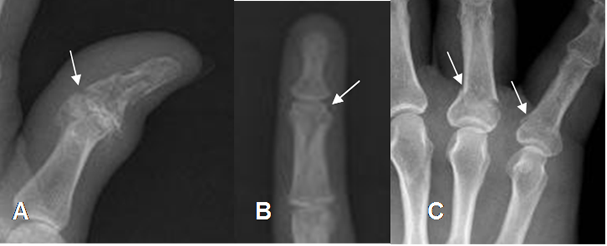

Fig 55. Fractura de los dedos.

A: Rx lateral. Fractura conminuta alrededor de la articulación interfalángica.

B: RX AP. Fractura oblicua del tercio distal de la falange media del 3º dedo.

C: Rx AP. Fracturas no desplazada en las bases de las falanges proximales de 2º y 3º dedo.